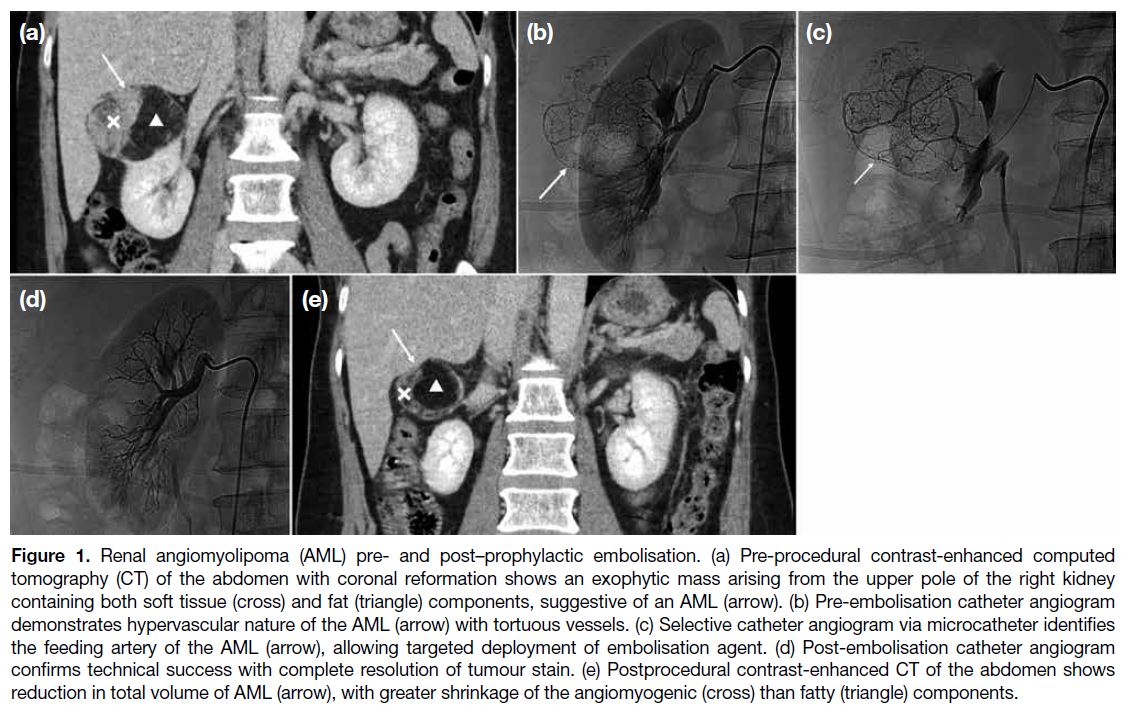

Renal angiomyolipoma (AML) is the most common

benign solid renal tumour.[1] The majority (approximately

80%) occur sporadically, while the rest (approximately

20%) are associated with phakomatoses, most

commonly tuberous sclerosis.[2] AML belongs to the

family of tumours with perivascular epithelioid cellular

differentiation.[3] It typically contains both angiomyogenic

and fatty components, with the latter readily identifiable

in computed tomography (CT) due to its hypoattenuating

nature (< -10 Hounsfield unit [HU]) [Figure 1].[4] [5]

Figure 1. Renal angiomyolipoma (AML) pre- and post–prophylactic embolisation. (a) Pre-procedural contrast-enhanced computed

tomography (CT) of the abdomen with coronal reformation shows an exophytic mass arising from the upper pole of the right kidney

containing both soft tissue (cross) and fat (triangle) components, suggestive of an AML (arrow). (b) Pre-embolisation catheter angiogram

demonstrates hypervascular nature of the AML (arrow) with tortuous vessels. (c) Selective catheter angiogram via microcatheter identifies

the feeding artery of the AML (arrow), allowing targeted deployment of embolisation agent. (d) Post-embolisation catheter angiogram

confirms technical success with complete resolution of tumour stain. (e) Postprocedural contrast-enhanced CT of the abdomen shows

reduction in total volume of AML (arrow), with greater shrinkage of the angiomyogenic (cross) than fatty (triangle) components.

It is well recognised that AML carries a risk of rupture

with bleeding, especially for larger tumours, which can

lead to fatal consequences.[6] [7] Treatment options include

transcatheter arterial embolisation and radiofrequency

ablation, as well as partial or radical nephrectomy.[8]

Selective arterial embolisation can be performed in an

emergency setting for AML with active bleeding. It can

also be a prophylactic treatment to reduce tumour size

and its risk of haemorrhage (Figure 1).[9] [10] It has been